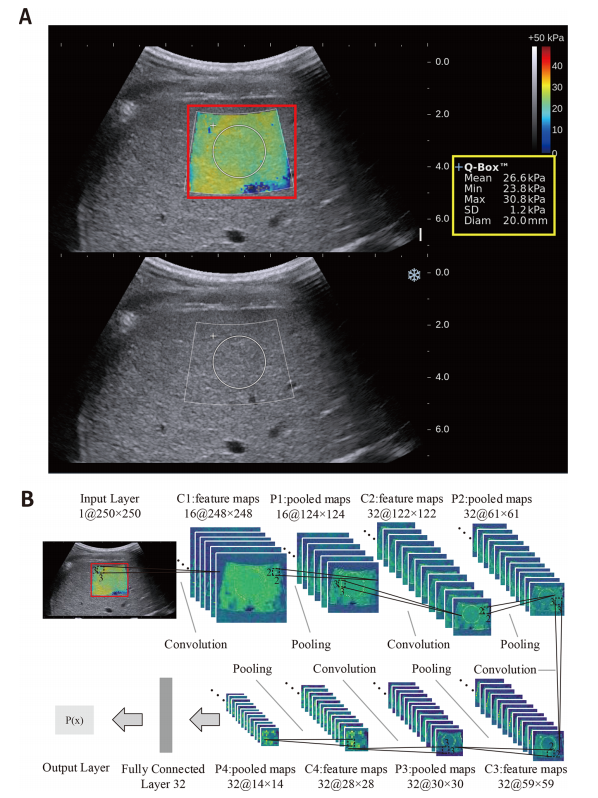

Figure 1 Illustration of the two-dimensional shear wave elastography (2D-SWE) measurement and the deep learning Radiomics of elastography (DLRE) flow chart. (A) The top shows the 2D-SWE region of interest (ROI) (pseudocolour area), Q-Box (white circle area within 2D-SWE ROI) and DLRE ROI (red square area). The obtained 2D-SWE values are displayed on the right yellow box. The bottom is the corresponding B-mode ultrasound image. (B) An input layer (DLRE ROI) is analysed by using four convolution-pooling procedures (C1-P1 to C4-P4), and then last pooled maps are fully connected with 32 neural nodes to calculate its probability for classification. The neural nodes and other parameters of the convolutional neural network (CNN) model were automatically optimised by using all 2D-SWE images in the training cohort.

图1 二维剪切波弹性成像(2D-SWE)测量和深度学习弹性成像放射组学(DLRE)流程图示例。(A) 顶部显示了2D-SWE感兴趣区域(ROI)(伪彩色区域)、Q-Box(2D-SWE ROI内的白色圆圈区域)和DLRE ROI(红色方形区域)。获得的2D-SWE值显示在右侧的黄色框中。底部是相应的B模式超声图像。(B) 输入层(DLRE ROI)通过四个卷积池化过程(C1-P1至C4-P4)进行分析,然后最后的池化图与32个神经节点完全连接,以计算其分类的概率。卷积神经网络(CNN)模型的神经节点和其他参数通过使用训练队列中的所有2D-SWE图像进行自动优化。